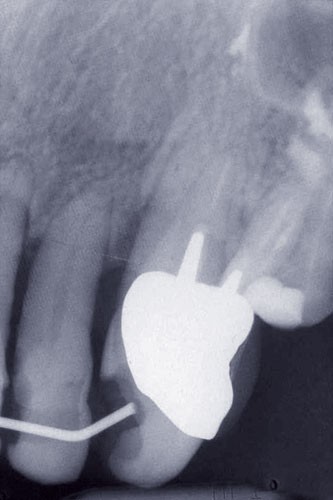

Une patiente âgée de 45 ans consulte à la fin des années 1990 avec une contention en échelle au maxillaire afin de soulager les mobilités des dents antérieures.

Les examens cliniques et radiographiques montrent une parodontite chronique généralisée (fig. 1a à m).

Nous décidons d’entreprendre une thérapeutique initiale parodontale classique dans tous les secteurs, y compris l’extraction de 24, un bridge de 45 à 48 avec 46 en pontique, un bridge complet de contention de 17 à 27 sur 11 piliers dentaires et une greffe épithélio-conjonctive sur 31. Cette dernière ne sera jamais réalisée. Le bridge maxillaire permettra de réduire le surplomb antérieur et d’améliorer le sourire de la patiente, ce qui constitue l’une de ses demandes.